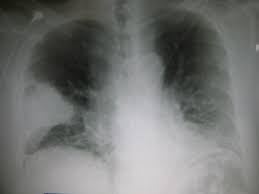

Contributors: Travis Barlock MD, Jeffrey Olson MS4 Feel free to use the cases below for your own practice. All of the scenarios are completely made up and designed to hit several teaching points. Case 1 25 M, presents to the ED with chest pain. Stabbing, started a few hours ago, substernal. Thinks it is GERD. After 2-3 minutes, pain worsens and radiates to the back. VS: BP 125/50 (Right arm 190/110). HR 120. RR of 18. Sat 98% on RA. Additional VS: Temp of 37.2, height of 6'5", BMI of 18. PMH: None, doesn't see a doctor. Meds: None FH: Weird heart thing (Mitral Valve Prolapse), weird lung thing (spontaneous pneumothorax), tall family members with long fingers and toes Physical Exam: Cards: Diastolic decrescendo at the RUSB, diminished S2. UE pulses are asymmetric, LE pulses are asymmetric, carotid pulses are asymmetric, BP is asymmetric MSK: Knees, elbows, and wrists are hypermobile. Imaging: CXR #1 normal, #2 widened mediastinum (no read yet but shows widened mediastinum), POCUS shows small effusion CTA/MRA doesn't come back until after the case. ECG: Sinus Tach Labs: NT-proBNP 500 pg/mL D-Dimer: 7000 ng/L CBC: Hemoglobin: 13.5 g/dL, WBC: 20,000/µL, Platelets: 250,000/µL Chem 7: Na 138, K, 5.7, Cl 102, Bicarb 17, BUN 45, Creatinine: 3.5 mg/dL, Glucose: 180 LFTs: Albumin 2.4, Total protein 5.5, ALP: 140, AST: 3500, ALT: 2800, TBili: 3.2, DirectBili: 2.4, Ca: 7.8 LDH: 2200 PT: 20.5, INR: 2.2, Fibrinogen: 170 5th gen High-Sensitivity Troponin: <3 Lactate: 7 mmol/L VBG: pH 7.22, paCO2 28, bicarb 15 Notes: Can have patient crash somewhere in middle and show 2nd xray Case 2: A 67-year-old female is brought to the ED by her daughter due to progressive weakness, confusion, and fatigue that have worsened over the past week. Unable to get out of bed and has become increasingly lethargic. Also having some nausea, constipation. The daughter denies any preceding illness, recent trauma, or travel. Does not know her meds but will head home to get them after talking with you. VS: BP 88/55 mmHg, HR 110, RR 20, O2 Sat 98% on room air. Additional VS: Temp 36.8°C. PMH: Hypertension, osteoarthritis, and depression. Physical exam: General: Thin, somnolent but arousable. HENT: Dry mucous membranes Neuro: Confused, A&Ox1 (self), hyporeflexia Labs (Includes many that would not return in the ED in case you want to take this case forward to the floor) CBC: WBC 9,500, Hb 16.5, Hct: 50%, Platelets 220,000 Chem7: Na 129, K 2.1, Cl 95, HCO3 34, Creatinine 1.6, BUN 40, Glucose 115 LFTs: normal Magnesium: 1.1 Calcium: 10.8 mg/dL (corrects to 12.8) iCal: 3.2 Phosphate: 2.3 mg/dL Albumin: 2 BUN:Cr ratio: 25 VBG: pH: 7.49, PaCO2 45, HCO3: 34 Lactate: 2.8 Serum Osmolality: 276 mOsm/kg (Osmolal gap of 2) Urine Osmolality: 550 mOsm/kg Urine Sodium (UNa): 10 mEq/L (low). Urine Potassium (UK): 25 mEq/L (elevated). Urine Chloride (UCl): 12 mEq/L (low). Urine Magnesium (UMg): 20 (Elevated). Urine Calcium (UCa): 50 in 24 hrs (Low) 100 cc of urine with foley FeNa Plasma renin activity: 15 mg/mL/hr (elevated), Aldosterone: 25 ng/dL (Elevated), ADH: Elevated, Diuretic screen: Positive for thiazides PTH: 8 (low), HsTrop: 32, Cortisol and ACTH: Normal. EKG: Hypokalemia features CXR: Normal Renal US: shows stones Improves with fluids Note: Can have daughter return with med list at some point including HCTZ, ibuprofen, and sertraline Case 3: Patient Presentation EMS Report: A 27-year-old male involved in a high-speed motorcycle collision is brought to the emergency department by EMS. The patient was found unconscious at the scene with evidence of severe thoracic and extremity trauma. He was intubated en route for airway protection due to altered mental status (GCS 7). VS: HR 130, BP 90/60, RR: bagging at 12 bpm, satting 88% on 100% FiO2 Primary Survey Airway: Endotracheal tube in place. Breathing: Decreased breath sounds on the left side with visible chest asymmetry and paradoxical chest wall movement. Circulation: Mottled extremities noted, with significant deformity of the right thigh. Pulses are diminished in the right leg Disability: GCS remains 7 (E1 V2 M4). Pupils equal and reactive. Exposure: Full-body examination reveals an open fracture of the right femur, multiple abrasions, and bruising over the chest wall. Vent alarms Peak Inspiratory Pressure (PIP) 40 cm H₂O (elevated) Plateau Pressure (Pplat) 35 cm H₂O (elevated) EtCO₂ (End-Tidal CO₂) 55 mmHg High-Pressure Alarm Triggering frequently Glucose 120 CBC: Hgb 8.9, Hct 27, WBC 14.2, platelets 220,000 VBG: pH 7.28, pCO2 33, bicarb 18, lactate 4.5 CXR with tension pneumothorax Patient improves after chest tube, pigtail catheter, or needle decompression. Ready to be transferred upstairs and O2 starts tanking again Vent alarms- second episode Peak Inspiratory Pressure (PIP) 35 cm H₂O (elevated) Plateau Pressure (Pplat) 30 cm H₂O (elevated) EtCO₂ (End-Tidal CO₂) 20 mmHg HR: 140, satting 84%, temp 38.5, ABG: pH 7.32, pCO₂ 30 mmHg, pO₂ 60 mmHg on 100% FiO₂, HCO₃⁻ 18 mmol/L (hypoxemia and metabolic acidosis). D-dimer: Elevated Thrombocytopenia: Platelets 90,000/µL. US shows blown right ventricle ECG shows new RBBB CT PE: Ground glass opacities, consolidation, centrilobular nodules, septal thickening, and fat-attenuating lesions. Note: Management is largely supportive care so once the diagnosis is made, end the case. References Carroll MF, Schade DS. A practical approach to hypercalcemia. Am Fam Physician. 2003 May 1;67(9):1959-66. PMID: 12751658. Coelho SG, Almeida AG. Marfan syndrome revisited: From genetics to the clinic. Rev Port Cardiol (Engl Ed). 2020 Apr;39(4):215-226. English, Portuguese. doi: 10.1016/j.repc.2019.09.008. Epub 2020 May 18. PMID: 32439107. Palmer BF. Metabolic complications associated with use of diuretics. Semin Nephrol. 2011 Nov;31(6):542-52. doi: 10.1016/j.semnephrol.2011.09.009. PMID: 22099511. Reed MJ. Diagnosis and management of acute aortic dissection in the emergency department. Br J Hosp Med (Lond). 2024 Apr 30;85(4):1-9. doi: 10.12968/hmed.2023.0366. PMID: 38708978. Roberts DJ, Leigh-Smith S, Faris PD, Blackmore C, Ball CG, Robertson HL, Dixon E, James MT, Kirkpatrick AW, Kortbeek JB, Stelfox HT. Clinical Presentation of Patients With Tension Pneumothorax: A Systematic Review. Ann Surg. 2015 Jun;261(6):1068-78. doi: 10.1097/SLA.0000000000001073. PMID: 25563887. Rothberg DL, Makarewich CA. Fat Embolism and Fat Embolism Syndrome. J Am Acad Orthop Surg. 2019 Apr 15;27(8):e346-e355. doi: 10.5435/JAAOS-D-17-00571. PMID: 30958807. Produced by Jeffrey Olson, MS4 Special thanks to Evan Fisch MD Get your tickets to Tox Talks Event, Sept 11, 2025: https://emergencymedicalminute.org/events-2/ Donate: https://emergencymedicalminute.org/donate/